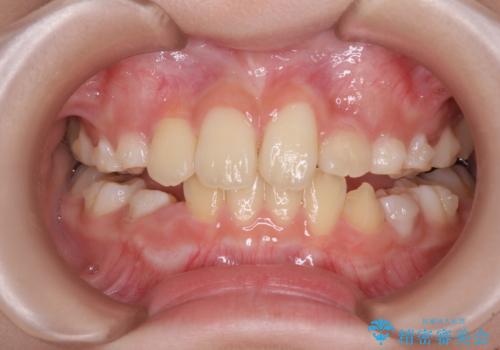

- 前歯の叢生を気にして来院された、小学校3年生女児の患者様です。

身長がやや低く、乳歯から永久歯への交換が少し遅い印象があったので、ワイヤー装置による1期矯正治療ではなく、乳歯も積極的に動かすことのできるインビザライン・ファーストにて治療を行うこととしました。

上顎前歯に過剰歯があったため、まずはその歯を抜歯し、傷が治癒したタイミングでインビザラインを発注することとしました。